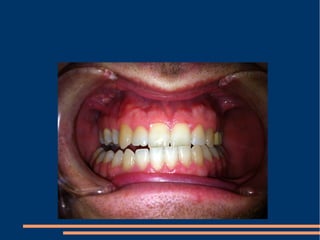

!!! A simple aesthetic treatment PPT